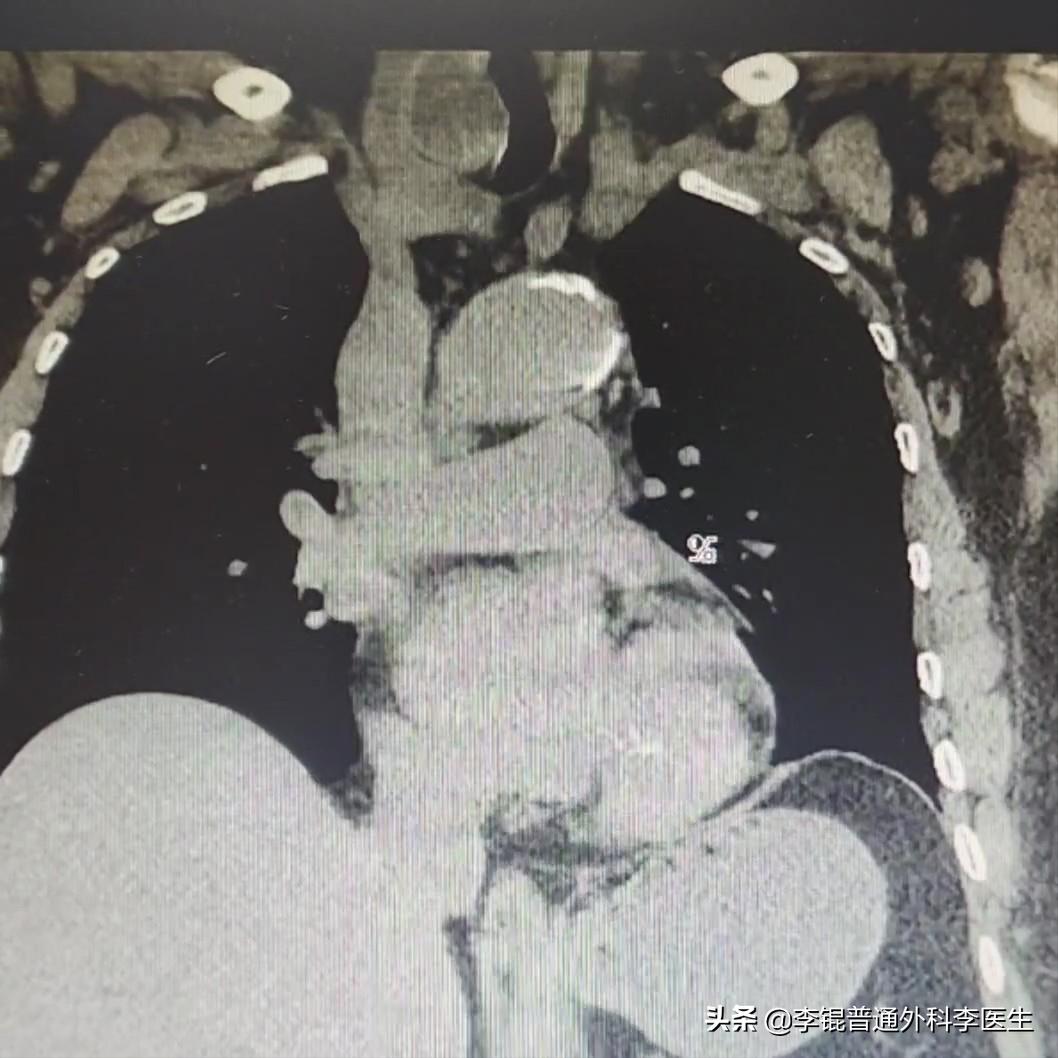

接连看了不同时间的CT检查,这个情况对比看起来会有个一个明显的加重。在CT上一侧的甲状腺有一个明显增大的结节并将气管挤到了一边。